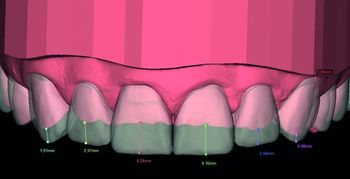

Digital Smile Design

Onlangs hebben wij ons eigen Digital Smile Design (DSD) ingevoerd waarbij we het voor iedere tandarts mogelijk maken om de patiënt de voordelen van het DSD-concept te geven zonder dat dit een tijdrovend en kostbaar werkproces met zich meebrengt. In ons concept verzorgen wij de planning en productie voor u, zodat u zich volledig kunt richten op de behandeling van de patiënt. Wij vinden optimale samenwerking met gemak voor onze klanten belangrijk.